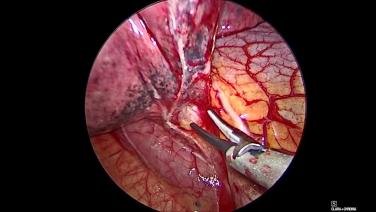

VATS Lobectomy Using HARMONIC™ 1100 Shears, ECHELON FLEX™ Powered Vascular Stapler, and SURGICEL™ Absorbable Hemostat